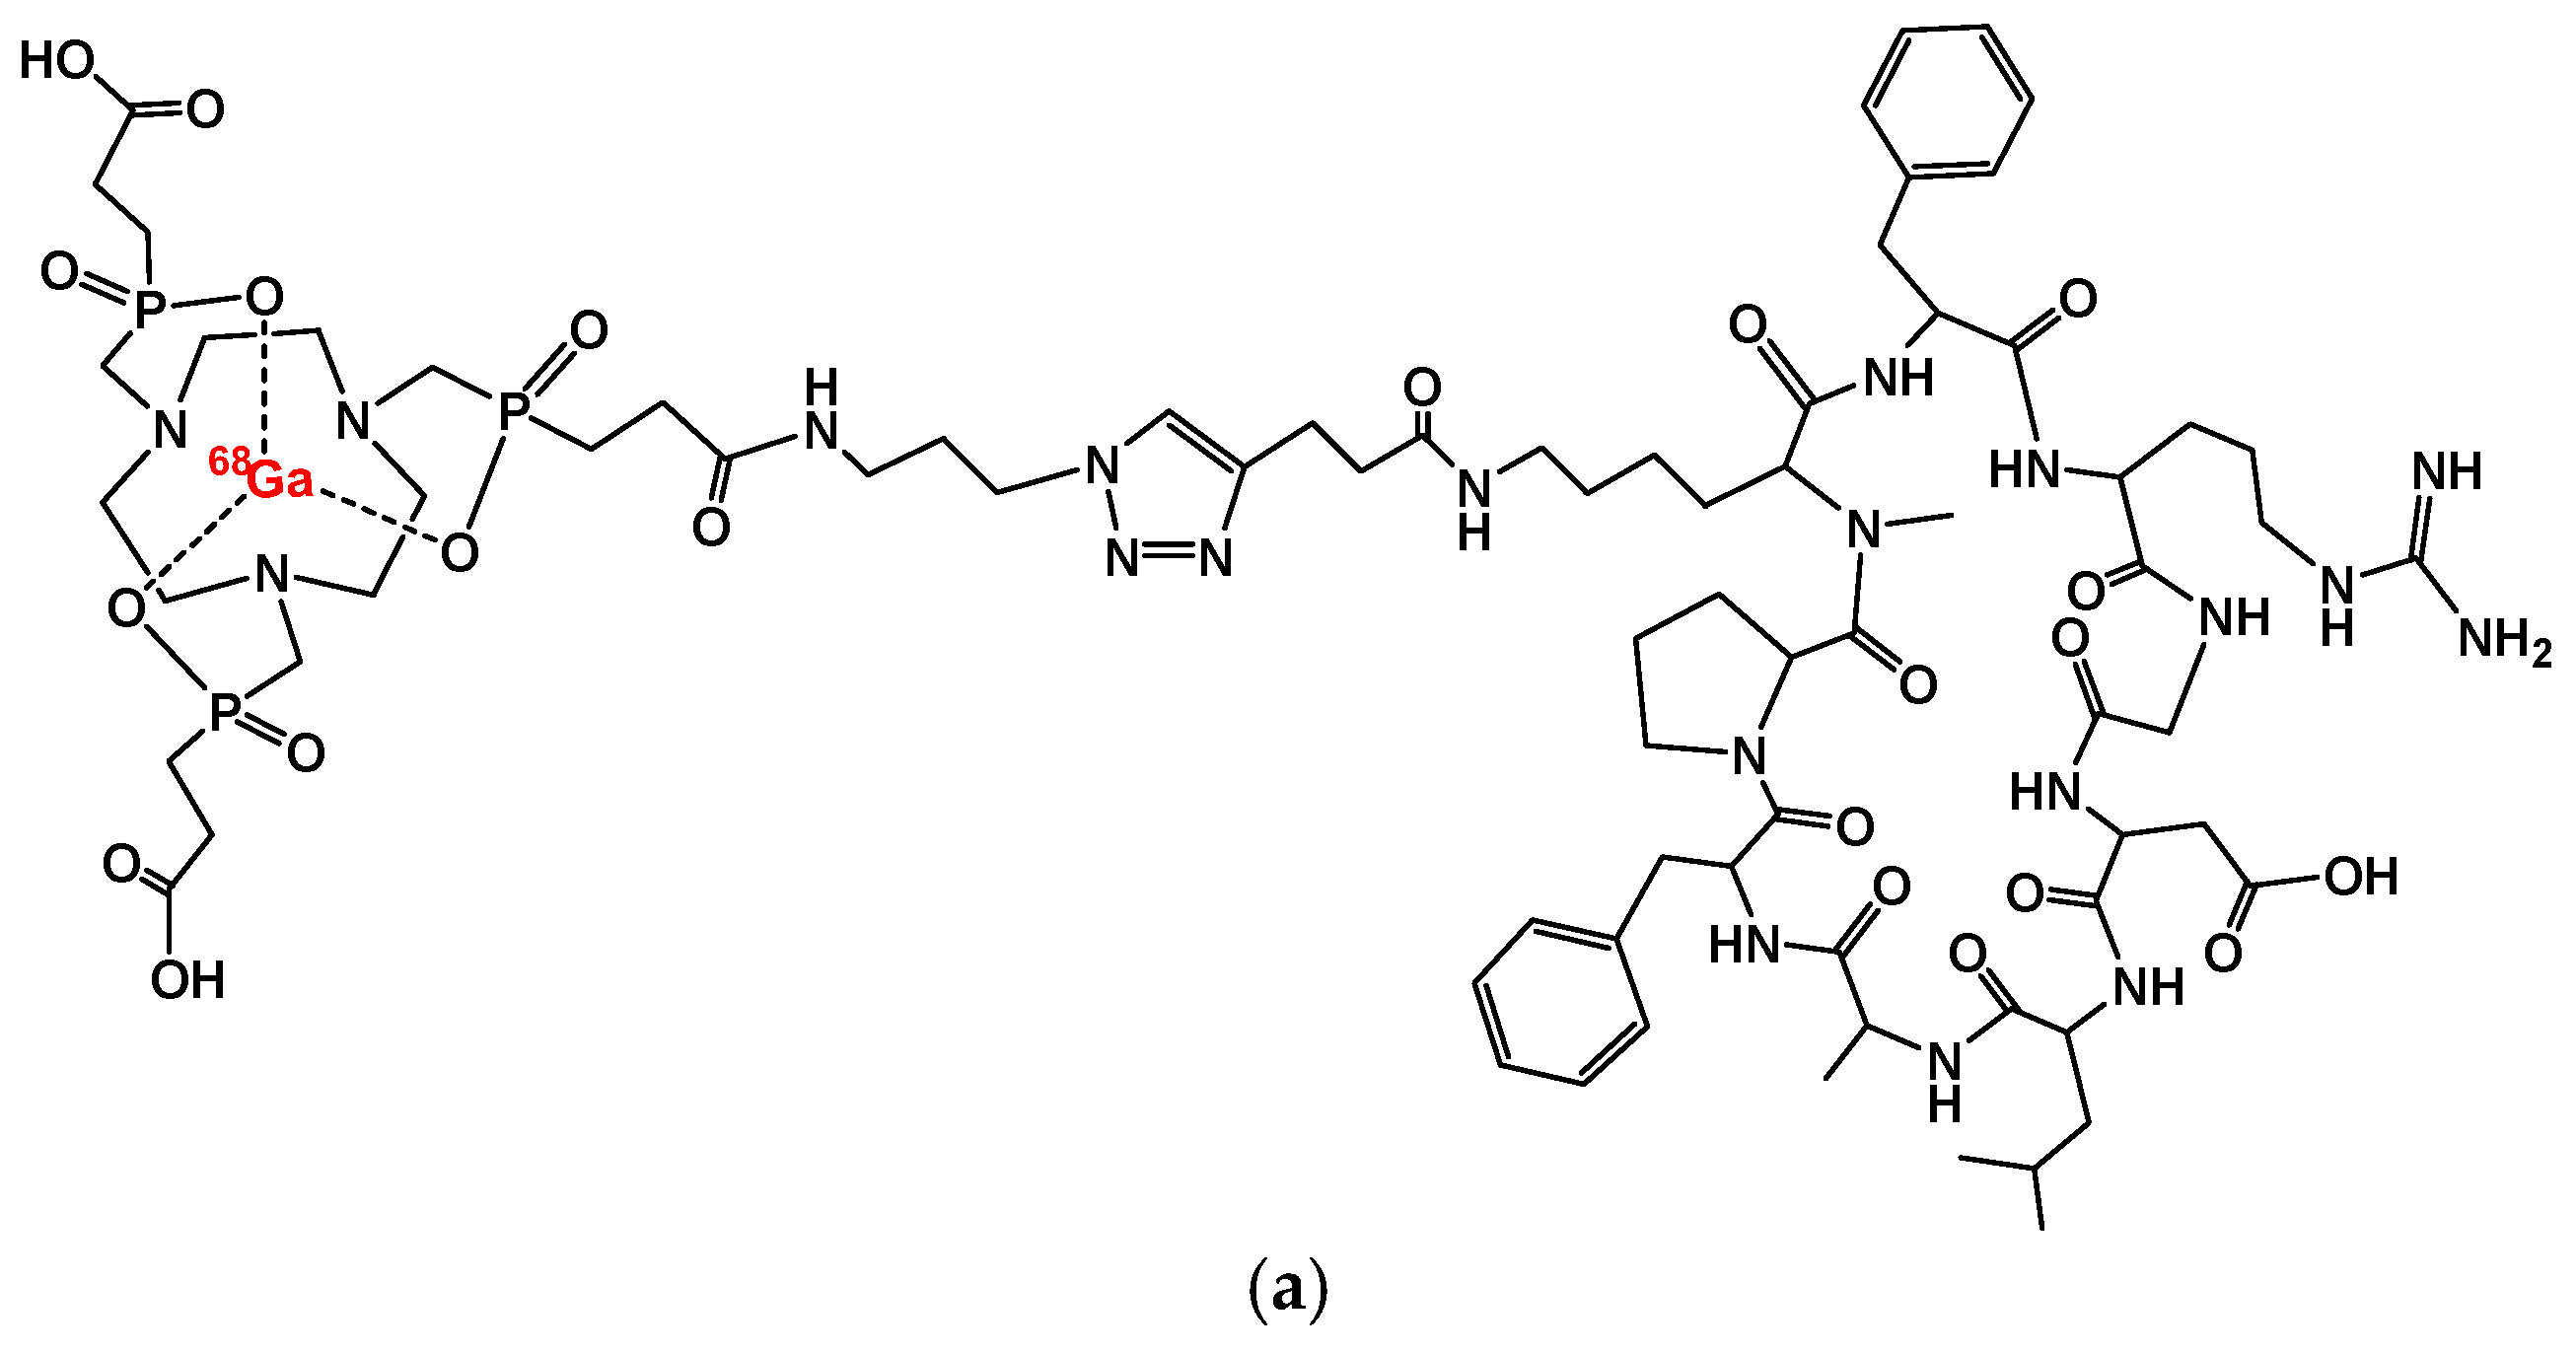

2. [68Ga]Ga-Trivehexin: A Radiochemical Insight